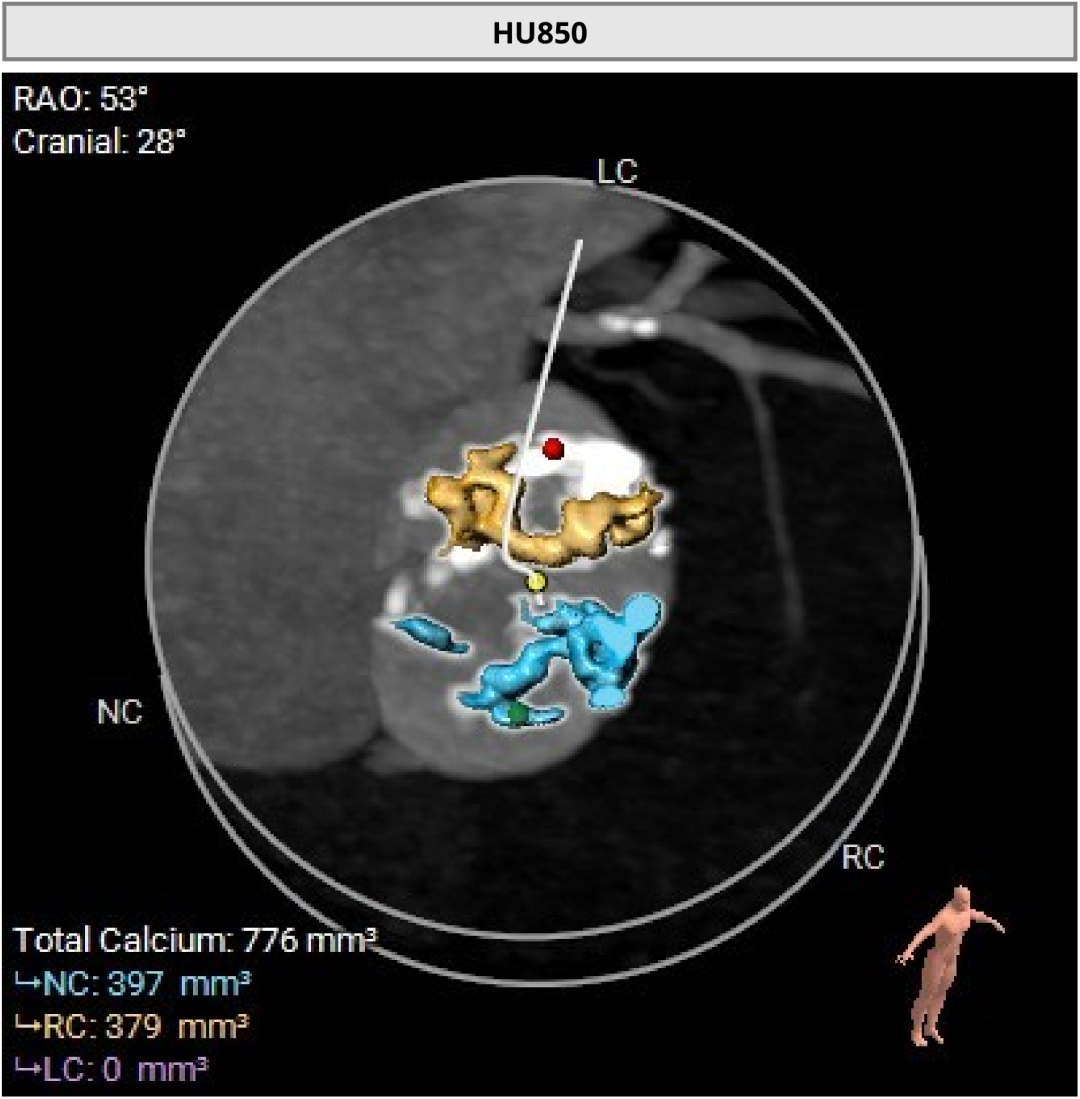

术前CT评估显示,患者瓣膜解剖条件总体具备经导管治疗基础,双侧冠脉阻塞风险偏低。

但与此同时,CT也提示患者存在冠状动脉三支严重钙化病变。也就是说,除了主动脉瓣问题外,供应心脏本身的血管也已经出现明显病变。如果不先处理冠脉问题,后续瓣膜治疗中的风险会进一步上升。

进一步评估显示,患者瓣膜狭窄程度重,瓣叶钙化明显,左心室腔径偏小,手术中对器械通过、瓣膜释放以及循环稳定性的要求都更高。团队结合术前影像和整体身体状况,制定了周密的介入治疗方案,并做好相关风险预案。

CT评估

瓣膜评估